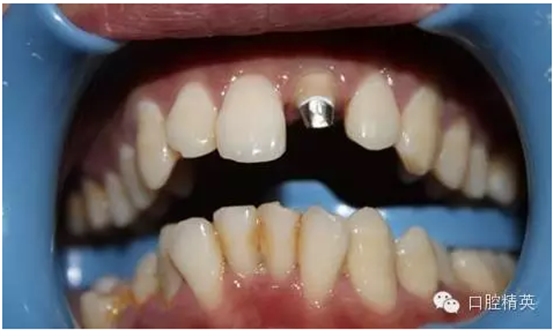

2:唇側(cè)觀,

3:鈷鉻金屬樁黏結(jié)后